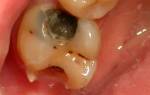

Глубокий кариес

В последней стадии развития кариеса возникает боль в области зубного нерва, который становится очень чувствительным к температуре пищи. Повреждение эмали и дентина расширяется. Однако, важно помнить, что боль при прямом контакте с зубом, при пережевывании пищи или по ночам, не является признаком глубокого кариозного поражения, а указывает на поражение десен. Лечение проводится по тем же принципам, что и в предыдущих случаях — удаление пораженной ткани, очистка эмали от налета и зубного камня, установка пломбы.

В статье представлены фотографии, которые наглядно объясняют, какие повреждения может вызвать этое заболевание и что такое кариес зубов. Каждая последующая стадия болезни требует все большего вмешательства со стороны врача.